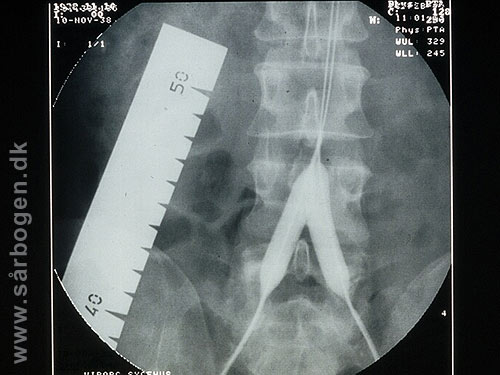

Zoom

Under PTA af iliacak...

Før PTA af iliacakar...